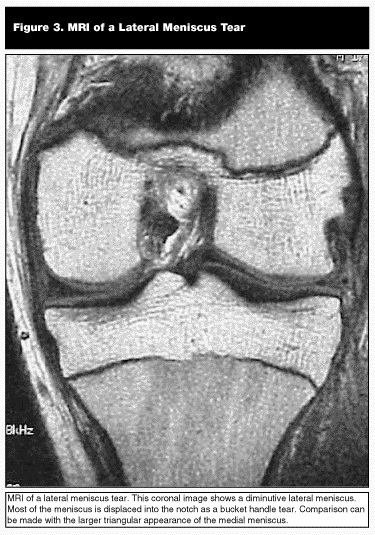

Meniscal Injuries. The medial and lateral meniscus act as shock absorbers and decrease the contact forces seen by the articular surfaces of the medial and lateral compartments of the knee.33 In addition, the medial meniscus is a secondary stabilizer to anterior tibial displacement. Injury to these structures compromises their function and may produce pain, locking, or catching symptoms. Often a small knee effusion is present. Joint line tenderness on the injured side, pain with full flexion of the knee, and a positive McMurray’s test helps with the diagnosis of the injury. In equivocal knee examinations, MRI can be helpful in securing a diagnosis.20,21,33 (See Figure 3.)